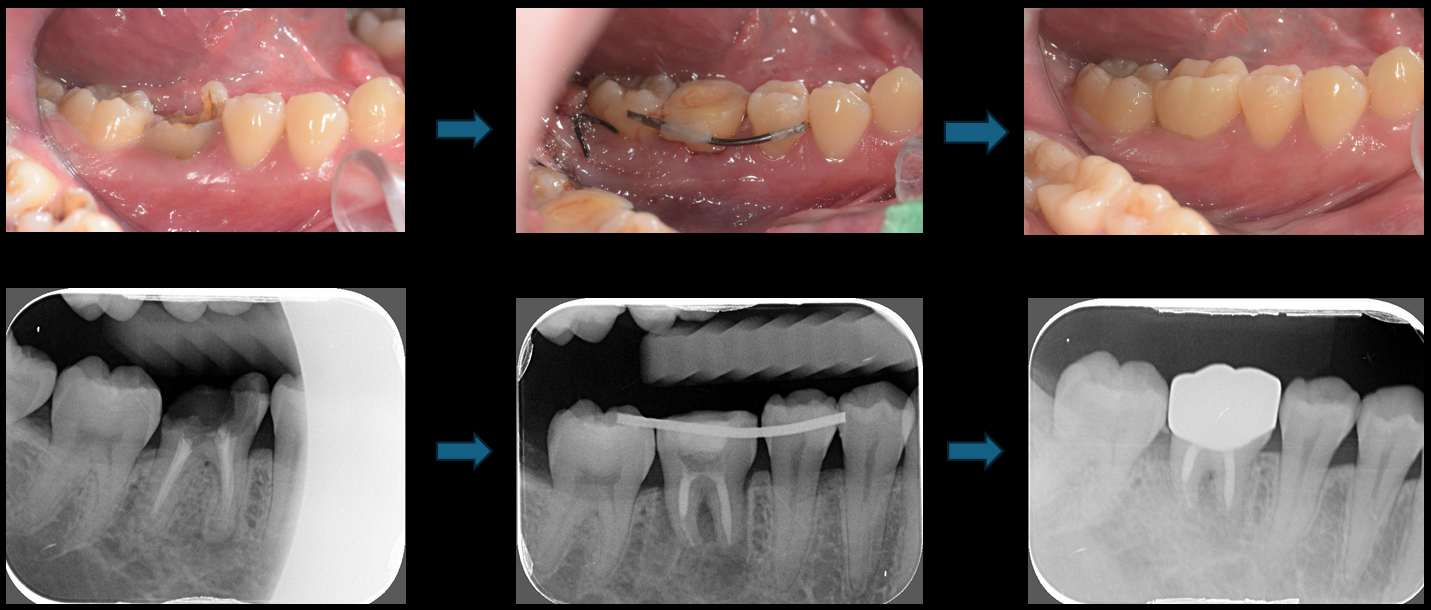

術前

術後

治療演進